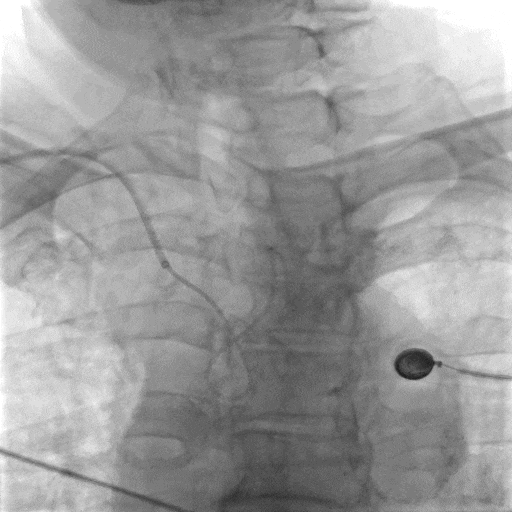

影像信息

右侧颈动脉系统造影显示:右侧颈内动脉起始段及颅内段未见狭窄;大脑中动脉显影可,远端血流速度可;大脑前动脉显影浅淡,前交通动脉未开放,右侧胚胎大脑后动脉。

左侧颈动脉系统造影显示:颈内动脉开口无狭窄,供血入颅;眼动脉段可见重度狭窄,狭窄率约70%;同侧大脑中动脉及大脑前动脉未见狭窄,前交通动脉开放代偿右侧大脑前动脉供血,左侧后交通动脉未开放。

左侧锁骨下动脉造影显示:左侧锁骨下动脉、椎动脉开口及颅内段均未见异常,基底动脉及各分支显影可。